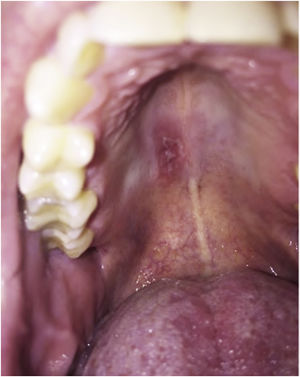

Primary immunodeficiencies that result from mutations in the genes encoding IL17 increase susceptibility to Candida infections. As expected, in patients who received anti-IL17 (brodalumab, secukinumab and ixekizumab) there was an increased incidence of candidiasis. However, most of the time the therapeutic response was good, without the need to withdraw the anti-IL17 treatment.51Fig. 2 depicts a case of oral candidiasis while using anti-IL17.